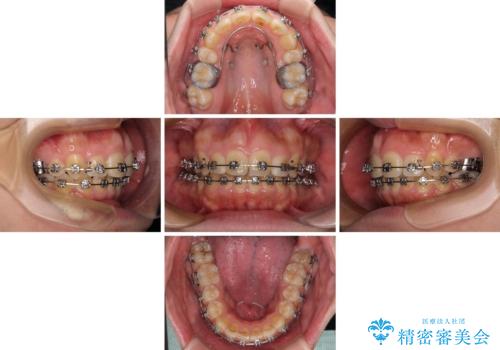

- 矯正装置

- メタルブラケット

マウスピース矯正でもワイヤー矯正でも対応可能でしたが、患者様の希望によりワイヤー装置による矯正治療を行うこととしました。

ワイヤー矯正ということで、上顎大臼歯を後方に移動するための補助装置を併用して、積極的に前歯を引っ込めていくこととしました。

上顎歯列全体がスムーズに後方移動でき、1年で治療を終えることができました。